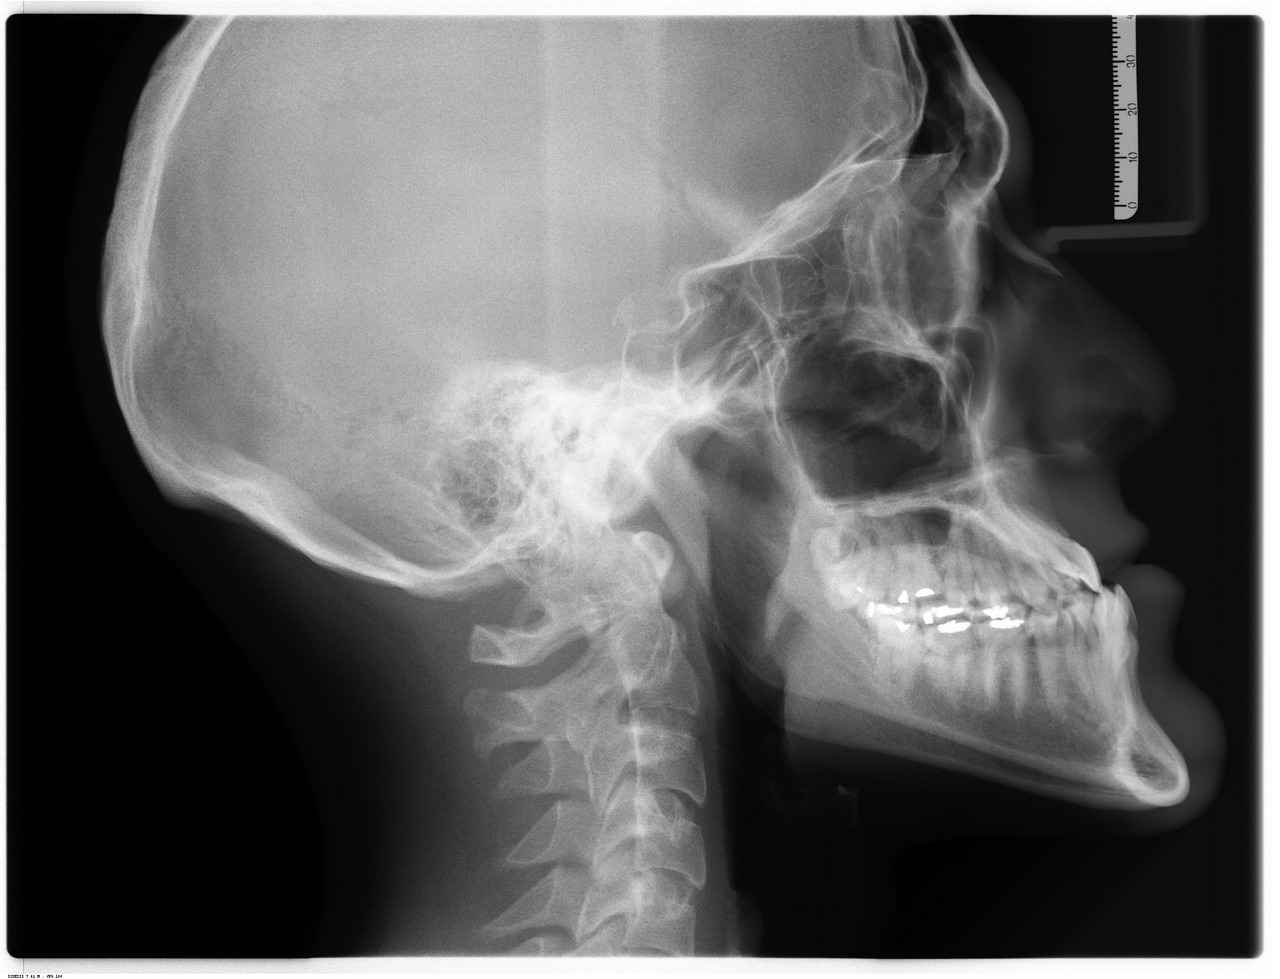

Birçok klinik, implant tedavisinden önce ön muayene ve danışmanlık hizmetleri sunmaktadır. Bu hizmetler, hastanın ağız sağlığını değerlendirmek ve implant tedavisine uygun olup olmadığını belirlemek için kritik öneme sahiptir. Ön muayene sırasında, diş hekimi hastanın ağız yapısını, kemik yoğunluğunu ve genel sağlık durumunu gözden geçirir.

Ön muayene, hastanın ağız sağlığını detaylı bir şekilde değerlendirmek için yapılan bir dizi test ve incelemeyi içerir. Bu süreçte, doktorlar hastanın diş yapısını, diş etlerini ve genel ağız sağlığını kontrol eder. Ayrıca, hastanın tıbbi geçmişi ve mevcut sağlık durumu da göz önünde bulundurulur. Bu aşamanın sağladığı bilgiler, tedavi planının oluşturulmasında kritik bir rol oynar.

- Hastanın Durumu: Ön muayene, hastanın ağız sağlığı ile ilgili problemlerini belirlemek için önemlidir. Özellikle diş eti hastalıkları, çene yapısı ve mevcut dişlerin durumu gibi faktörler, implant tedavisinin uygulanabilirliğini etkileyebilir.

- Risk Değerlendirmesi: Muayene sırasında yapılan değerlendirmeler, olası komplikasyonları önceden tespit etmeye yardımcı olur. Bu sayede, tedavi sürecinde karşılaşılabilecek sorunlar minimize edilir.